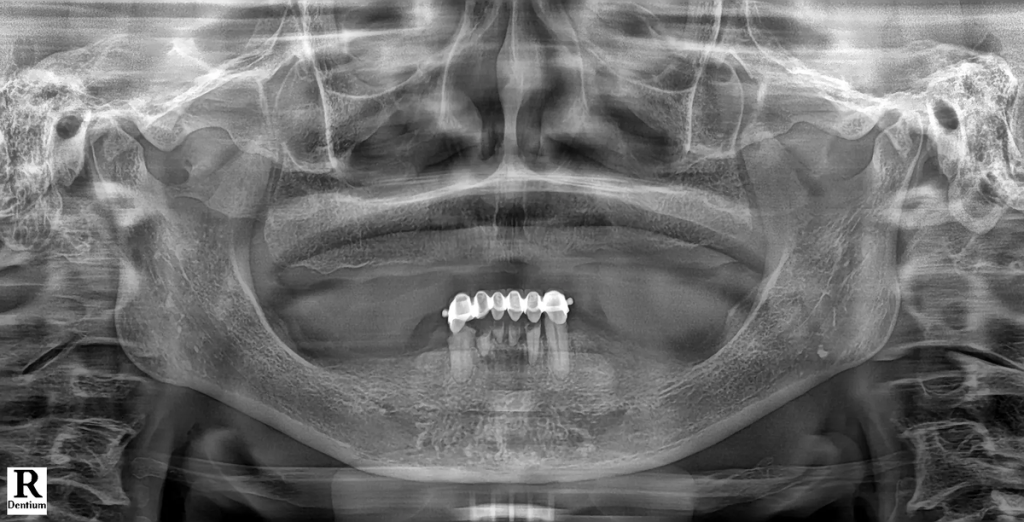

제작된 가이드를 이용해 계획된 위치에 임플란트를 식립한 뒤, 당일 또는 단기간 내 임시 보철을 연결합니다. 여러 개의 임플란트를 하나의 보철 구조로 묶기 때문에 저작 안정성이 빠르게 확보되고, 치료 기간 동안 일상생활의 불편도 크게 줄어듭니다.

• 치료 후 변화 “이제는 음식 종류를 가리지 않고 먹을 수 있어서 삶의 만족도가 확실히 달라졌습니다.” 디지털 스캔 데이터를 기반으로 3D 치료 계획을 수립한 뒤, 컴퓨터 가이드 수술로 임플란트를 정확한 위치에 식립했습니다. 이후 CAD/CAM 기술로 제작된 풀아치 보철물을 장착하며 치료가 진행되었고, 적은 방문 횟수로 치료를 마칠 수 있었습니다.